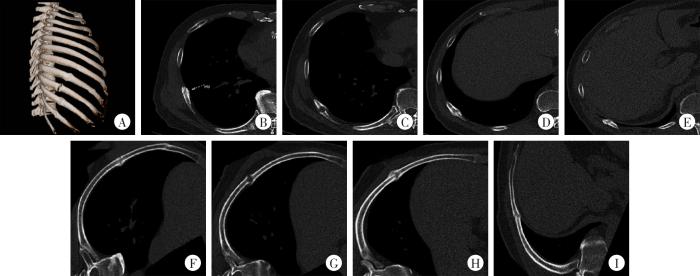

图3

3种图像后处理技术的比较

男性患者,59岁,胸部外伤5个月余。A:右侧肋骨VR图像;B:右侧第8肋骨MPR图像;C:右侧第9肋骨MPR图像;D:右侧第10肋骨MPR图像;E:右侧第11肋骨MPR图像;F:右侧第8肋骨CPR图像;G:右侧第9肋骨CPR图像;H:右侧第10肋骨CPR图像;I:右侧第11肋骨CPR图像。

Fig. 3

Comparison of three image post-processing techniques